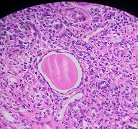

HISTOPATHOLOGY

What is the lesion seen in this section ?

Ans to previous : (August 2025)

Tumour embolus in a lymphatic channel.